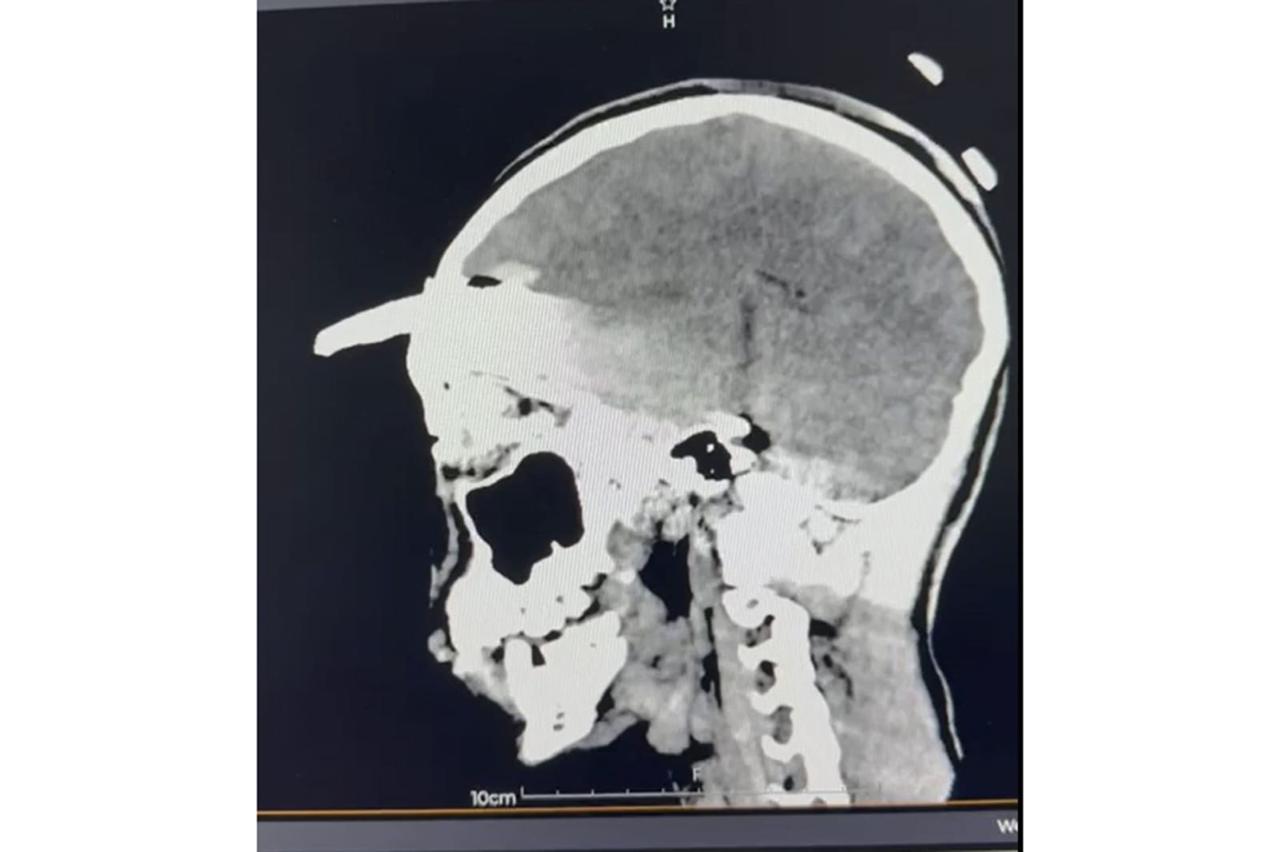

El 2 de noviembre, Yael fue trasladado desde el municipio de Acanceh al Hospital General Regional (HGR) No. 12 del IMSS en Mérida, donde la directora, doctora Claudia González Ramírez, y un equipo de especialistas ya se encontraban preparados para recibirlo y atender la emergencia. Tras confirmarse un traumatismo craneoencefálico severo, se realizaron estudios

inmediatos que determinaron la profundidad y ubicación del objeto.

Los estudios de imagen permitieron ubicar con precisión el objeto, mientras que el menor recibía tratamiento con antibióticos de amplio espectro para prevenir infecciones asociadas con el instrumento metálico.

Después de un análisis minucioso y una planeación quirúrgica, el doctor Ornelas González dirigió un procedimiento de cuatro horas que permitió retirar exitosamente el machete curvo sin afectar tejido cerebral, en una intervención que confirmó la pericia y capacidad del equipo médico.